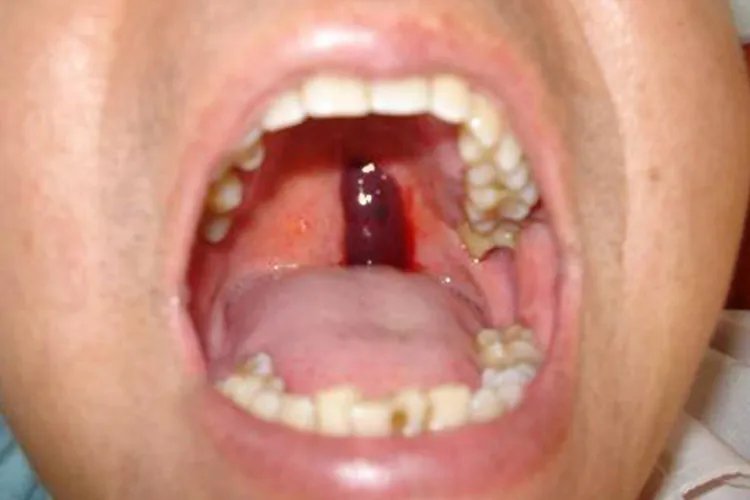

血小板减少性紫癜包括特发性血小板减少性紫癜、继发性或症状性血小板减少性紫癜、血栓性血小板减少性紫癜。特发性血小板减少性紫癜1.急性型多见于2~6岁儿童,起病急骤,可有畏寒发热,皮肤和黏膜发生广泛严重的出血,见群集淤点、大片淤斑,甚至血肿,于碰撞部位更多见,口腔黏膜可出现血疱,舌缘血疱咬破后,可出血不止。任何器官均可发生出血,常见于鼻腔、齿龈、胃肠道、泌尿生殖道出血。